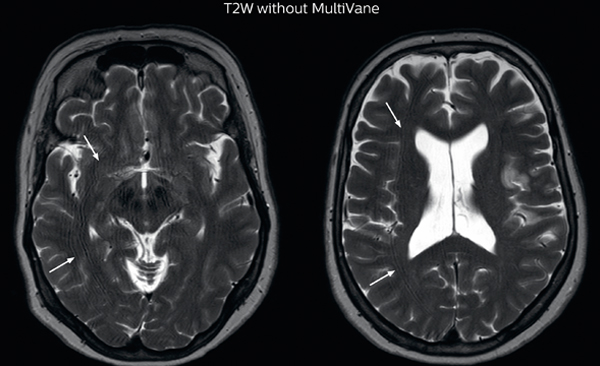

MRI motion artifact reduction in brain

The images made with MultiVane XD show significant reduction in motion artifact compared to the T2-weighted images without MultiVane below them.

Scanned on Ingenia 3.0T

UVM case 2 motion artifact MultivaneXD

UVM case 2 motion artifact